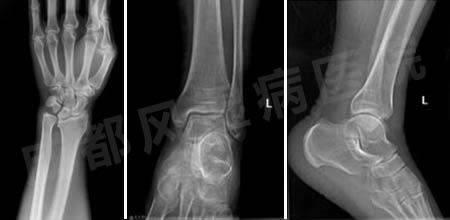

我院DR示:双手骨质疏松,部分掌指、近指关节狭窄,模糊,小囊样变,关节软组织肿胀,双踝软组织肿胀,间隙变窄,双膝关节软组织肿胀,关节间隙变窄,骨质疏松,关节缘骨赘形成。

(图:刘先生入院后,DR示指关节狭窄,双踝关节肿胀模糊)